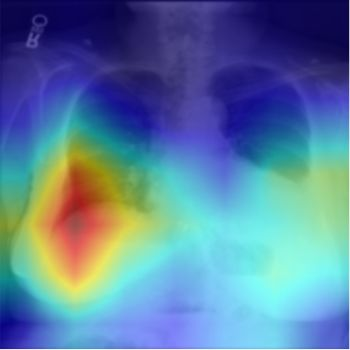

The way humans attend to, process and classify a given image has the potential to vastly benefit the performance of deep learning models. Exploiting where humans are focusing can rectify models when they are deviating from essential features for correct decisions. To validate that human attention contains valuable information for decision-making processes such as fine-grained classification, we compare human attention and model explanations in discovering important features. Towards this goal, we collect human gaze data for the fine-grained classification dataset CUB and build a dataset named CUB-GHA (Gaze-based Human Attention). Furthermore, we propose the Gaze Augmentation Training (GAT) and Knowledge Fusion Network (KFN) to integrate human gaze knowledge into classification models. We implement our proposals in CUB-GHA and the recently released medical dataset CXR-Eye of chest X-ray images, which includes gaze data collected from a radiologist. Our result reveals that integrating human attention knowledge benefits classification effectively, e.g. improving the baseline by 4.38% on CXR. Hence, our work provides not only valuable insights into understanding human attention in fine-grained classification, but also contributes to future research in integrating human gaze with computer vision tasks. CUB-GHA and code are available at https://github.com/yaorong0921/CUB-GHA.